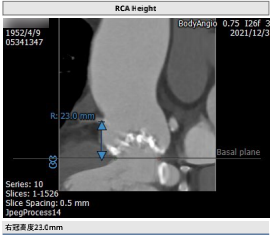

李妍主任提出该患者为TYPE 0型二叶瓣,重度钙化,主要分布于瓣叶交界,升主动脉较宽,窦部结构大,双侧股动脉入路均有钙化,术中注意轻柔操作,同时主动脉弓部大折角,大弯侧钙化侧瓣叶钙化重,可能存在输送系统过弓困难及跨瓣困难及瓣膜下滑风险术中密切注意,逐决定抓捕器辅助,24球囊预扩,选择植入VitaFlow Liberty ™30瓣膜,根据术中瓣膜形态及有无瓣周漏,做后扩准备。手术投照角度选取右窦最低,LAO结合CRA体位,保证看到窦底最底点,提高定位精度。

从右侧股动脉完成主动脉瓣根部造影,结果显示重度钙化,窦部结构大